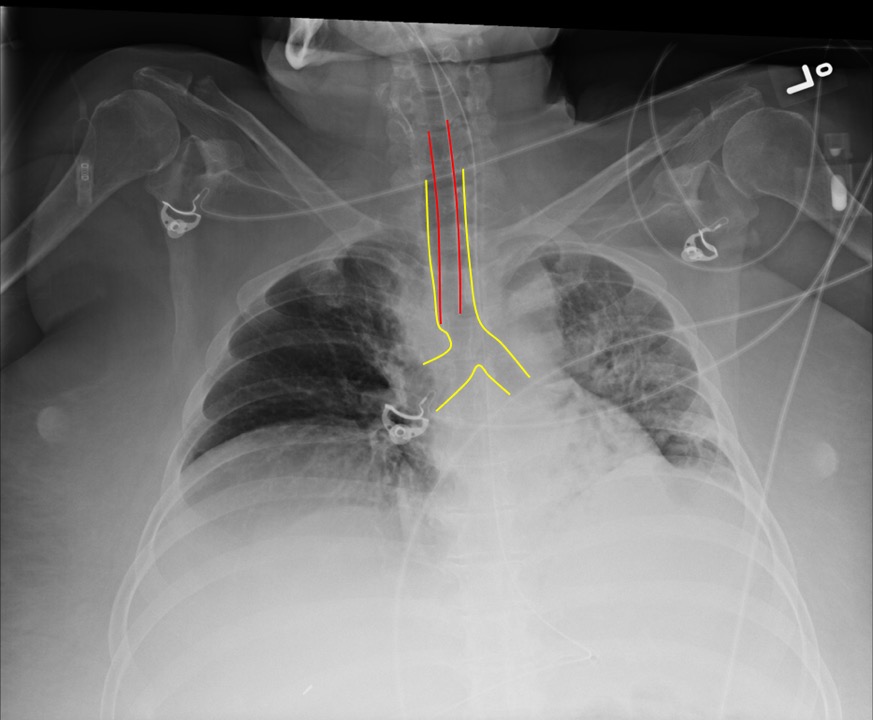

Endotracheal tubes

Endotracheal tube (ETT) tip should sit 3-5cm above the carina. The ETT can be too high above the carina and will need to be advanced, or too deep into the right mainstem and need to be pulled back.

Intubation with Good Position of ETT

Red = ETT; Yellow = Trachea and Bronchi

Right mainstem bronchus intubation